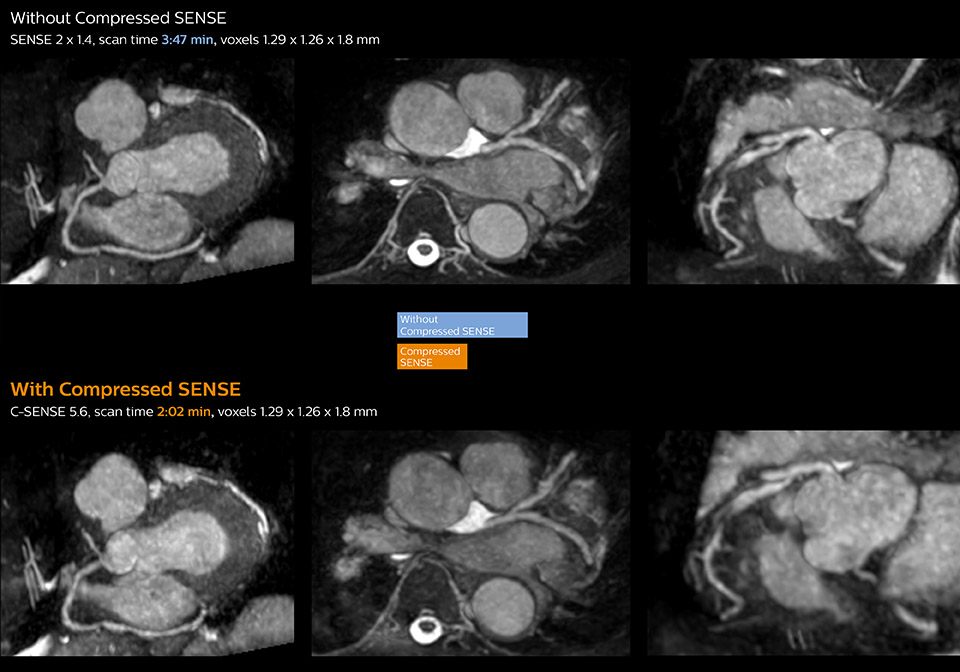

These images of a patient with acute myocardial infarction images were acquired on Ingenia 1.5T with and without Compressed SENSE.

These images with and without Compressed SENSE were acquired on Ingenia 1.5T.

“Compressed SENSE has now been implemented in all cardiac exams. Thanks to the acceleration, fewer breath holds are now needed, or breath hold times are shortened. This reduces the burden of the exam for cardiac patients, without affecting the quality of information required for cardiac function analyses,” he says. “Because it’s easier for patients to comply with the breath hold times” “In our previous cardiac cine sequence, we were acquiring two slices during one breath hold. With Compressed SENSE, we increased this to four slices per breath hold. It is also possible to shorten scanning time using a C-SENSE factor 6 without sacrificing image quality.”

Dr. Koshi Miyake, cardiologist, explains that scanning of patients with cardiac arrhythmia can be challenging, as scanning times can become very long due to the varying heart rate. So his most important motive to implement Compressed SENSE in cardiac MRI exams was to reduce the burden of breath holds for the patient, while maintaining high image quality. He hopes this can also help to reduce motion caused by the difficulty for patients to hold their breath.

“Typically, in scans with high contrast, such as 2D balanced TFE cine, a quite high C-SENSE factor may be used. When we tried a higher C-SENSE factor, we saw still no significant influence on cardiac ejection fraction, but 2D image quality started to decline. For coronary imaging, we use a C-SENSE factor of 3 in 3D balanced TFE, or even up to 4 when contrast is high.”